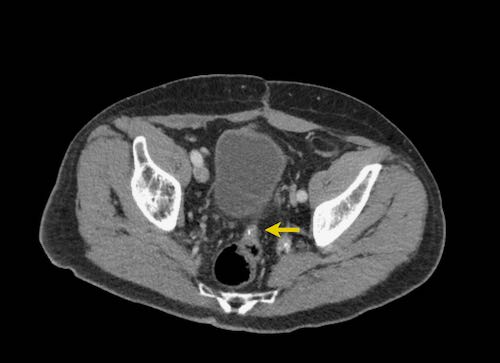

Ca lâm sàng 2

Cuộn qua các lát cắt.

Bạn có thể phát hiện tất cả các tổn thương cấy ghép phúc mạc không?